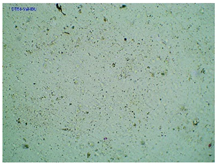

Some structural modifications of IBU dispersed in the adhesive matrix showed micrometric particle size which was recorded by microscopy. The observations were carried out on the day of receiving the patch, after 7 days simulating the conditions of the period of using the patch on the skin, and after 3 months, which was to reproduce the storage conditions of obtained patches in constant temperature (20 °C). Table 2 presents the crystallization of drugs quantitatively from the patch in the form of microscopic images, while Table 3 summarizes the sizes of the observed drug crystals. First, on receiving patches with new ibuprofen modifications, no significant differences in drug crystal sizes were observed compared to the reference patch containing unmodified ibuprofen (TP-IBU). The exception was the patch containing IBUNa which contained large drug crystals. This may be due to their poor solubility in solvents or the adhesive matrix in preparing adhesive compositions. After 7 days of observing patches not protected with siliconized foil, i.e., under conditions simulating their use, such as air access, small crystals are visible in all patches, regardless of the ibuprofen modification applied. Additionally, in this case, TP-IBUNa is distinguished by an increase in the size of the crystals during the seasoning. The final observation was on patches protected with siliconized foil, which were observed after 3 months. In this case, crystals of similar size were observed on the day of their preparation. Therefore, no drugs were synthesized from the patches, proving their stability during storage.

Microscopic observation of patch samples containing various structural modifications of ibuprofen during the seasoning time.